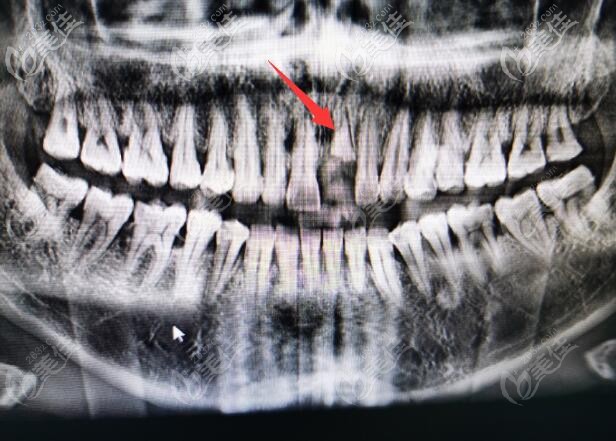

前門牙種植好后拍的CT照片▼

在復(fù)診的時(shí)候,我還專門問了他,是不是前牙種植成功率低?

李醫(yī)生說,前牙和后牙種植比較大的區(qū)別就是,前牙要考慮到美學(xué)因素,在美學(xué)基礎(chǔ)上設(shè)計(jì)骨組織。

很多醫(yī)生在給顧客種植的時(shí)候,只考慮顧客的牙槽骨,等一期手術(shù)結(jié)束,才發(fā)現(xiàn)出問題了。種植牙到是愈合的挺好,不過美觀度欠佳。